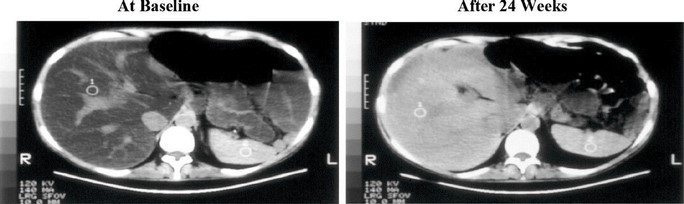

Upon conversion of the quantification of computed tomography (CT) values to magnetic resonance imaging proton density fat fraction (MRI-PDFF), significant differences in the least square (LS) mean change from baseline in estimated MRI-PDFF were observed in the IV Choline Chloride group in comparison to placebo group at Week 4 through Week 24, demonstrating a clinically meaningful and statistically significant reduction in steatosis. When LS mean percent changes from baseline in MRI-PDFF were compared between treatment groups, significant differences in LS mean changes (range, 31.7% to 53.6%) were observed from Weeks 4 to 24 with p-values of 0.0009 to 0.0297 favoring the IV Choline Chloride group.

Figure 3. Liver CT Images: Before and After Treatment with IV Choline Chloride

Alkaline Phosphatase: